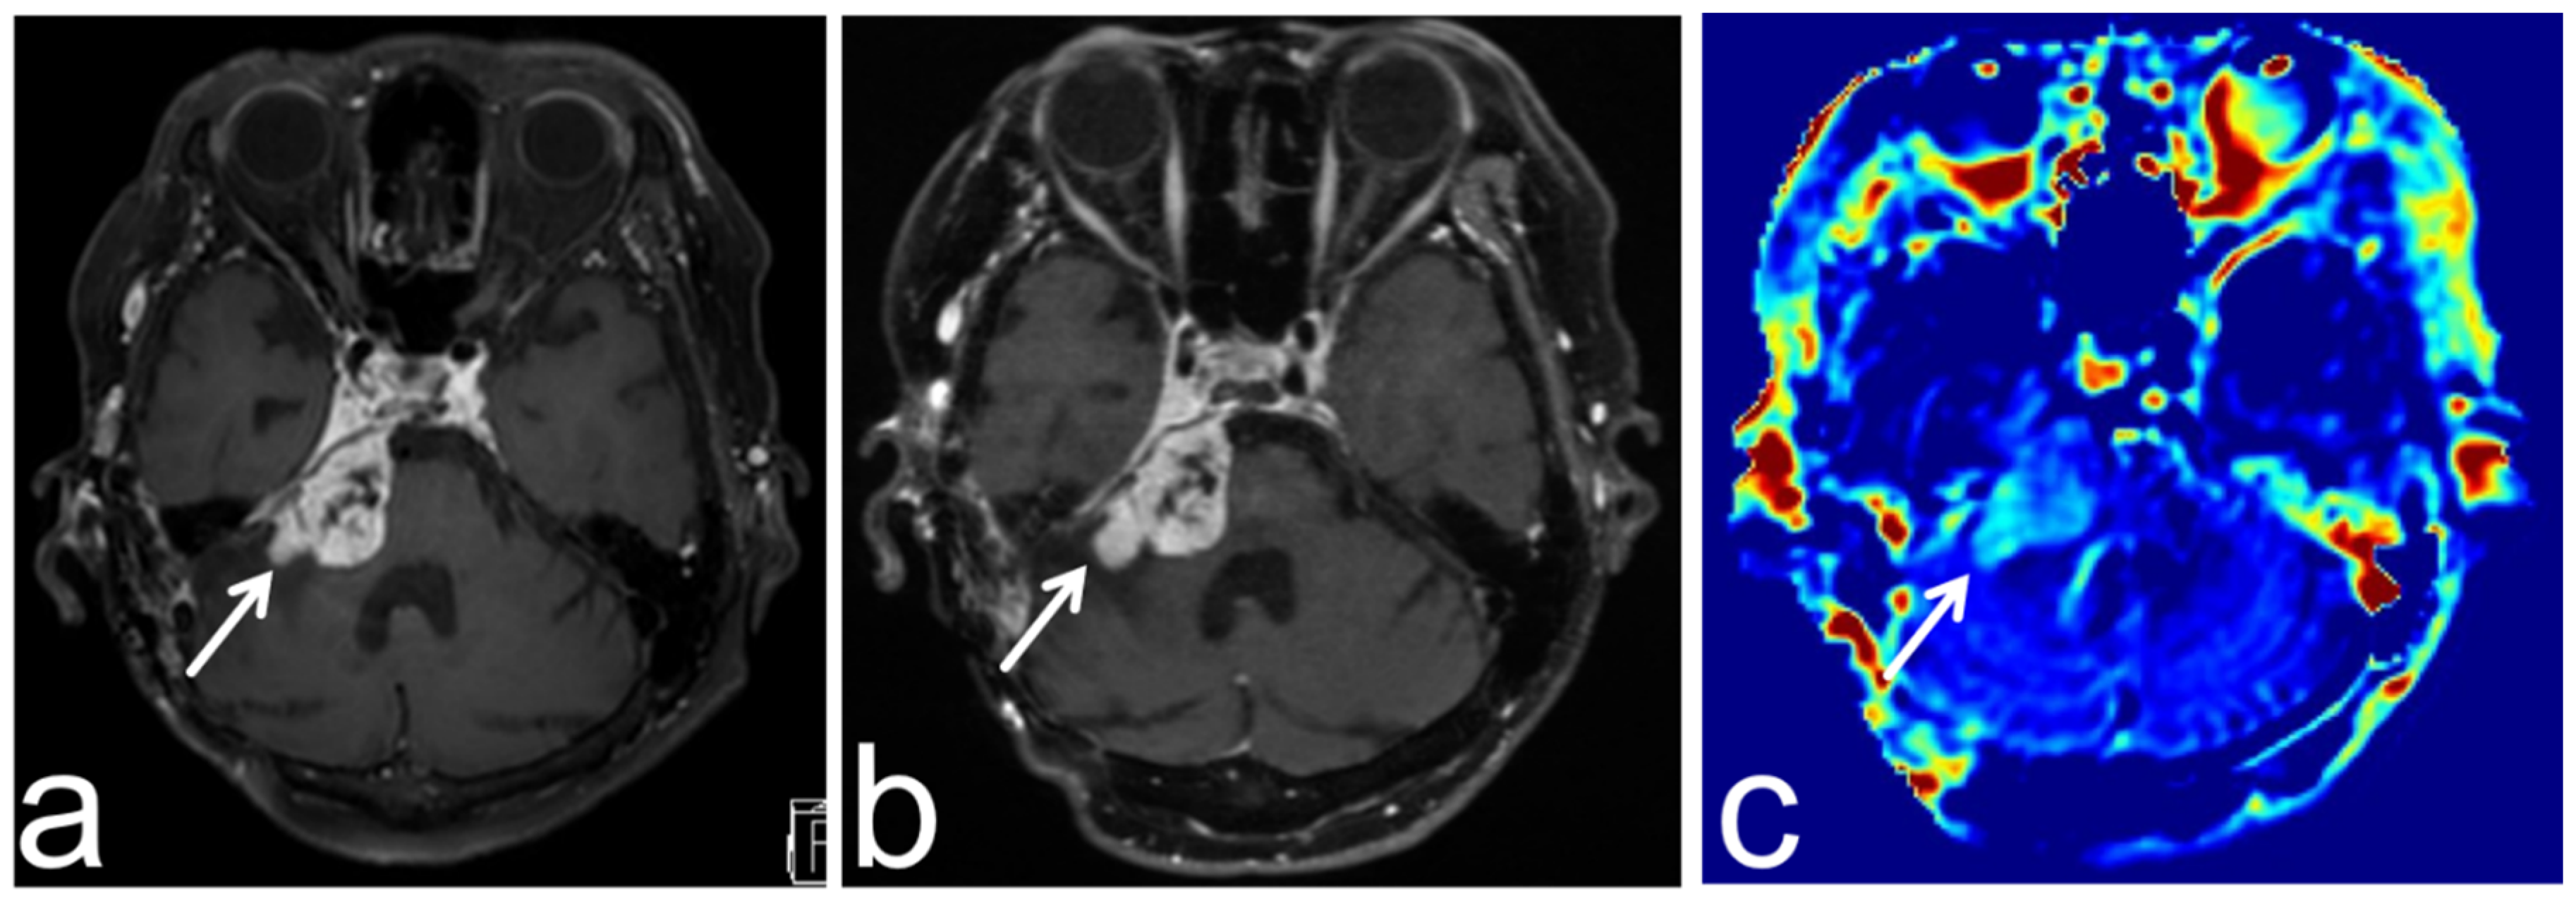

8.4. Progressive Multifocal Leukoencephalopathy